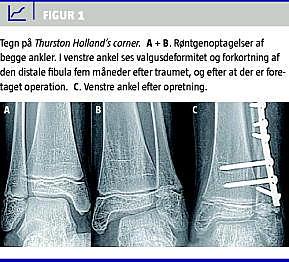

En tiårig pige kom til skade på en skiferie. Hun blev undersøgt lokalt, hvor man fandt, at hun havde smerter i og hævelse af den laterale del af venstre ankel. Hun var ikke i stand til at støtte på den venstre fod. Et røntgenbillede viste intet abnormt. På mistanke om en epifyseskiveskade af den distale fibula anlagde man en bagvedliggende skinne. Patienten blev efter få dage set på hjemstedssygehuset, hvor man havde mistanke om en epifyseskade af den distale fibula. På baggrund af dette blev patienten udstyret med en crusgips i fem uger. Efter afbandagering havde hun fortsat smerter i anklen. Klinisk var der hævelse og palpationsømhed. Patienten blev fulgt op klinisk, og på grund af manglende bedring blev der efter tre måneder foretaget en magnetisk resonans-skanning. Denne gav ikke nogen forklaring på symptomerne, men man kunne se, at der var dannet en bro i epifyseskiven. Et nyt røntgenbillede af begge ankler, der blev taget efter fire måneder, viste breddeøget afstand i det mediale ledkammer i den skadede side (Figur 1 A + B). Ved yderligere gennemgang af patientens røntgenbillede fandt man en SH type II i den distale fibula, som var helet med sammenvoksning i epifyseskiven i den distale fibula. Dette medførte forkortning af fibula i forhold til tibia og bevirkede udvikling af valgusdeformitet i anklen. Patienten blev opereret seks måneder efter skadetidspunktet. Der blev foretaget osteotomi af den distale fibula og akut forlængelse og resektion af sammenvoksningen af epifyseskiven i den distale fibula. Patienten blev fulgt i ti måneder, hvor man fandt normal akse og bevægelse i anklen, og hun var derefter symptomfri (Figur 1 C).

Traumatisk skade af epifyseskiven i den distale fibula er et sjældent fænomen, der dog kan forekomme i forbindelse med skade af anklen hos børn [3]. Det er en udfordring at kunne skelne mellem epifyseskivefrakturer og distorsioner i den distale del af fibula [4, 5]. I 1929 beskrev Holland vigtigheden af Thurston Holland's corner- tegn i forbindelse med diagnosticeringen af SH type II [1]. Thurston Holland's corner refererer til det trekantede metafysære fragment, som ses i forbindelse med SH type II. Werenskiold & Bergenfeldt beskrev et »lamellar«-tegn, som er den tynde skal, der især i den distale fibula ses i forbindelse med visse typer af epifyseskivefrakturer [1]. Disse tegn kan henlede opmærksomheden på en mulig epifysefraktur. Det er desuden vigtigt at kende forholdene mellem den distale del af tibia og fibula. I den normale ankel er den laterale malleolspids 3-4 mm mere distalt end den mediale malleolspids, og fibulaepifyseskiven er på samme niveau som ankelledfladen [5]. Som følge af epifyseskiveskader kan der forekomme forkortning af fibula. Dette kan medføre progressiv valgusdeformitet og instabilitet af ankelleddet.